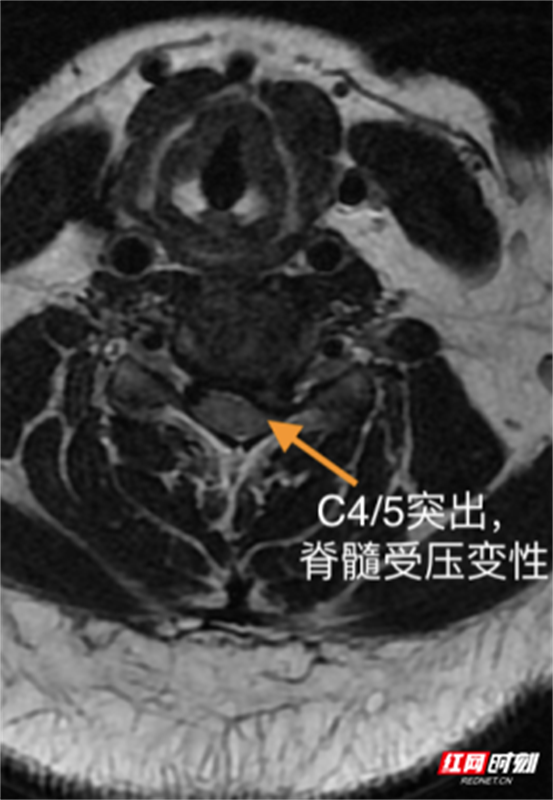

随后,患者相继出现头晕、头痛、呕吐及会阴区麻木。医疗团队紧急启动预案,查CT与MRI结果排除脑出血与急性脑梗死,最终确诊为颈3/4、颈4/5椎间盘突出压迫脊髓,伴脊髓部分变性,解除脊髓压迫为治疗关键。